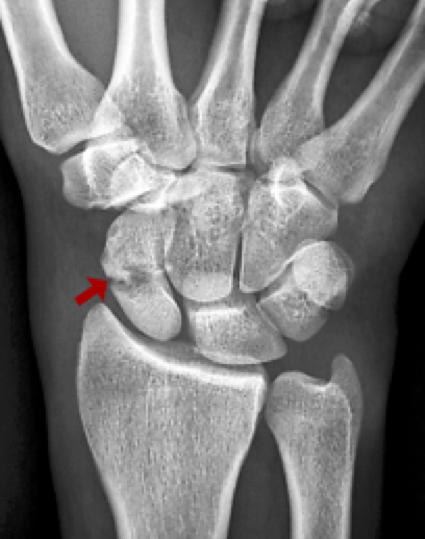

Scaphoid Fracture

The scaphoid is the most commonly fractured carpal bone, accounting for 60–70% of carpal fractures. It typically fractures from a fall on an outstretched hand and is most common in young active men aged 15–40. The presentation is often subtle — pain in the anatomical snuffbox (base of thumb, radial wrist) — and is frequently dismissed as a sprain.

Up to 20% of scaphoid fractures are not visible on initial X-rays. An undiagnosed or inadequately treated scaphoid fracture has a high risk of non-union (failure to heal) due to the precarious blood supply of the proximal pole. Non-union leads predictably to SNAC (scaphoid non-union advanced collapse) wrist arthritis. Early diagnosis with MRI and appropriate treatment prevents this complication.

• X-ray (AP, lateral, scaphoid views) — may miss up to 20% of fractures